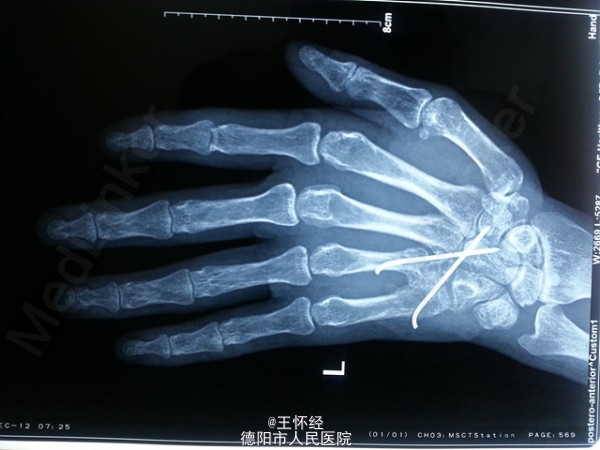

左手脱套伤一例

患者青年男性,机器所致左手脱套伤,急诊入院行手术治疗,术后4月复查功能尚可。